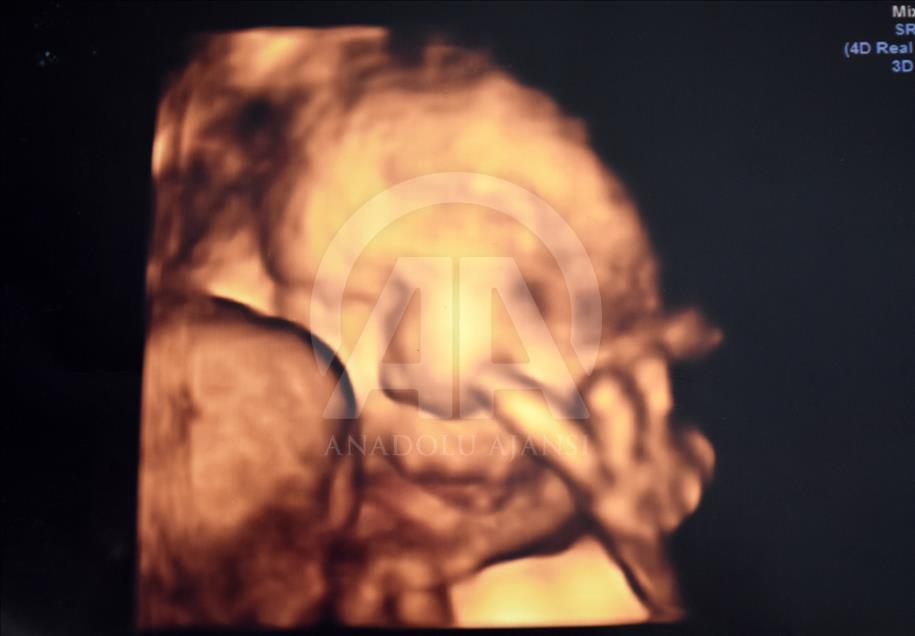

Anne karnındaki bebeklerin ilginç ultrason görüntülerini yakalayan ve bu görüntülerden özel bir köşe oluşturan kadın hastalıkları ve doğum uzmanı Doç. Dr. Gökalp Öner'in, yaklaşık 4 bin fotoğraflık koleksiyonu bulunuyor. Doç. Dr. Öner, AA muhabirine yaptığı açıklamada, sadece bir koleksiyon sahibi olmanın değil, anne ve babalara güzel bir hatıra oluşturmanın mutluluğunu da yaşadığını belirterek, "Doğumdan sonra aileler bizi ziyarete geldiği zaman kendi köşeleri olsun ve orada fotoğraf çektirelim istedik. Böylece, yaklaşık 4 bin ultrason fotoğrafına ulaştık." dedi. ( Müzahim Zahid Tüzün - Anadolu Ajansı )